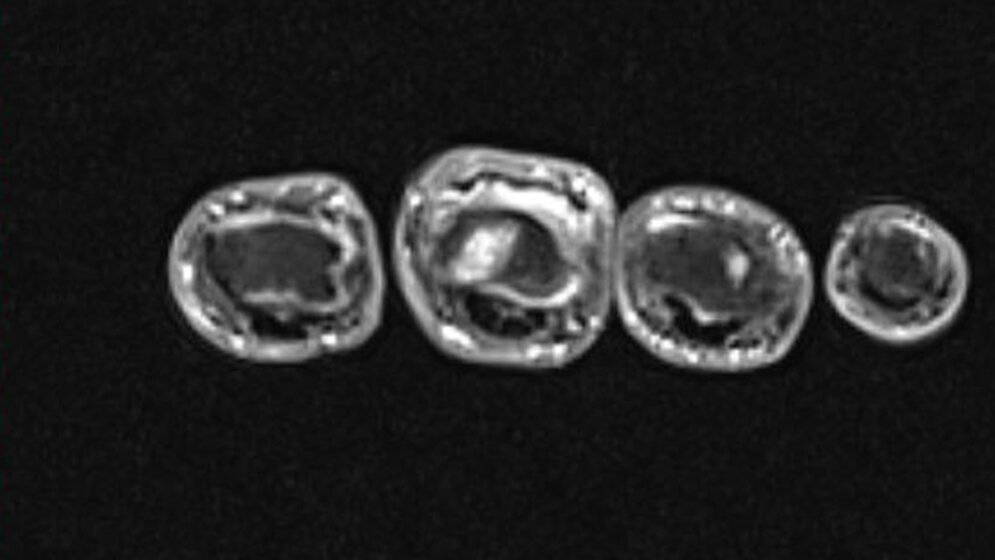

Im Fall 6 konnte die MRT die aktive Arthritis der Interphalangealgelenke einer 59-jährigen Patientin mit schmerzhafter Schwellung der Fingergelenke besonders in den KM-unterstützten fettunterdrückenden Sequenzen nachweisen (Abb. 6.1 und 6.2).

Abb. 6.1: koronales MRT nach KM (T1 TSE FS, 1,5 T): Arthritis des proximalen Interphalangealgelenks 3 und 4 sowie des DIP-Gelenks 2

Abb. 6.2: transversales MRT nach KM (T1 TSE FS, 1,5 T): Arthritis des proximalen Interphalangealgelenks 3 besonders deutlich